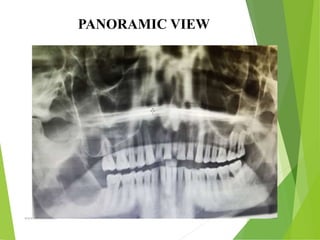

PANORAMIC VIEW

(revealed a large multilocular radiolucent area extending from the 44

to the right coronoid process including the ascending ramus area)

RADIOGRAPHIC FINDINGS

• Ameloblastomas are osteolytic & present as

unilocular or multilocular.

• Well circumscribed by bony radiopaque borders

• Margins are usually well defined & sclerotic

• Root resorption & tooth displacement.

• Displacement of the neurovascular bundle

• Cortex shows thinning and often severe expansion

• Involvement of the antrum is seen as an opacification.